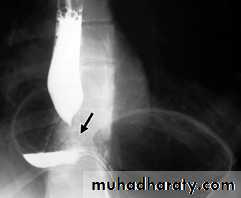

Achalasia

It is a neuromuscular abnormality result from failure of relaxation of the cardiac sphincter, which present at barium examination as a smooth , tapered narrowing always at the lower end of esophagus (bird beak or rat-tail appearance).There is associated dilatation of the esophagus, which often shows absent peristalsis. The dilated esophagus usually contains food residues and may be visible on CXR. The lungs may show consolidation and bronchiectasis from aspiration of the esophageal contents. The stomach gas bubble is usually absent.